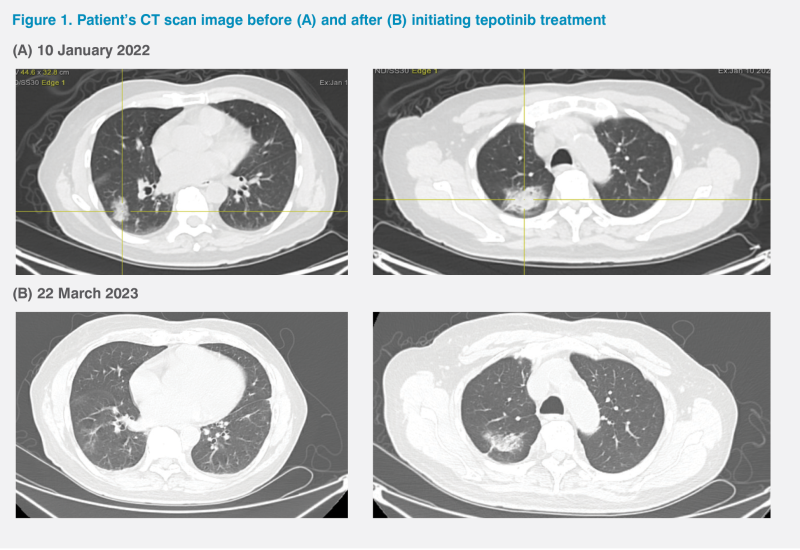

An 80-year-old Chinese male, a long-term smoker with no significant medical history, was found to have a right lung mass on a routine chest X-ray in August 2021. A CT scan of the chest revealed a dominant right lower lobe mass (3.3 x 2.3 x 2.7 cm) with multiple bilateral lung nodules. CT-guided fine needle aspiration cytology (FNAC) of the right lower lobe mass performed on 2 December 2021 confirmed adenocarcinoma, while a PET-CT scan on 10 January 2022 showed a right lower lobe tumour with metastases to the left hilar and mediastinal lymph nodes and both lungs. (Figure 1A) Next-generation sequencing (OncoSnap Nonet) identified MET exon 14 (METex14) skipping mutation. The programmed death ligand 1 (PD-L1) tumour proportion score (TPS) was 0 percent. The patient was diagnosed with stage IV non-small-cell lung cancer (NSCLC) harbouring a METex14 skipping mutation. His Eastern Cooperative Oncology Group performance status (ECOG PS) was 0.

The patient began treatment with tepotinib (450 mg QD) on 29 March 2022. Reassessment CT scan on 20 September 2022 showed responding disease with reduction in size of all lung metastases and mediastinal lymph nodes. His disease remained stable, as confirmed by a subsequent CT scan on 22 March 2023. (Figure 1B)